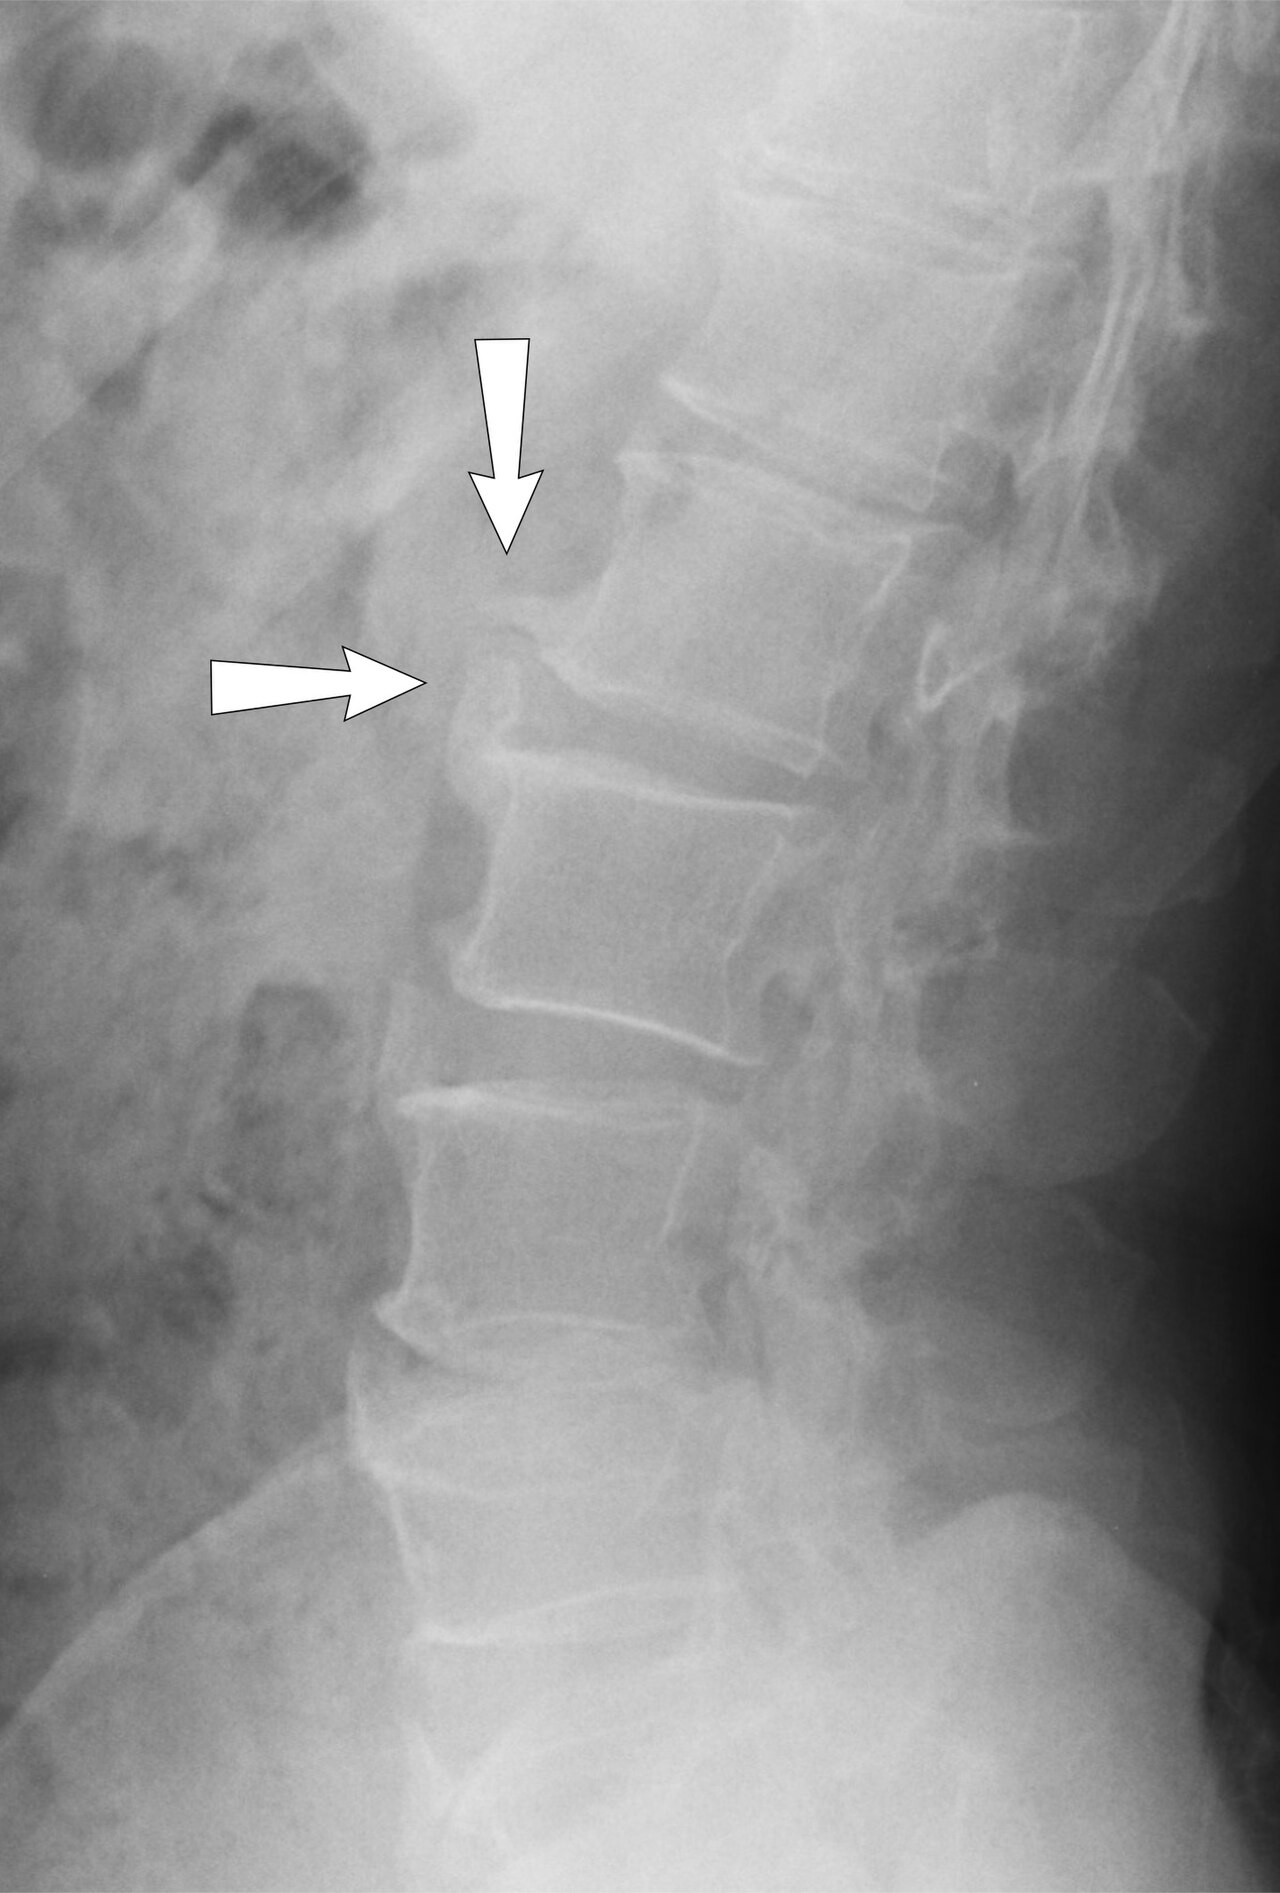

L4-L5 posterolateral disc herniation compressing the L5 nerve root with disc desiccation, annular tear, and...